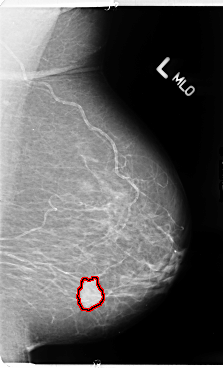

B_3108_1.LEFT_MLO

LEFT_MLO LINES 4784 PIXELS_PER_LINE 2896 BITS_PER_PIXEL 12 RESOLUTION 50 OVERLAY

FILE: B_3108_1.LEFT_MLO.OVERLAY

TOTAL_ABNORMALITIES 1

ABNORMALITY 1

LESION_TYPE MASS SHAPE ROUND MARGINS SPICULATED

ASSESSMENT 4

SUBTLETY 5

PATHOLOGY MALIGNANT

TOTAL_OUTLINES 1

BOUNDARY